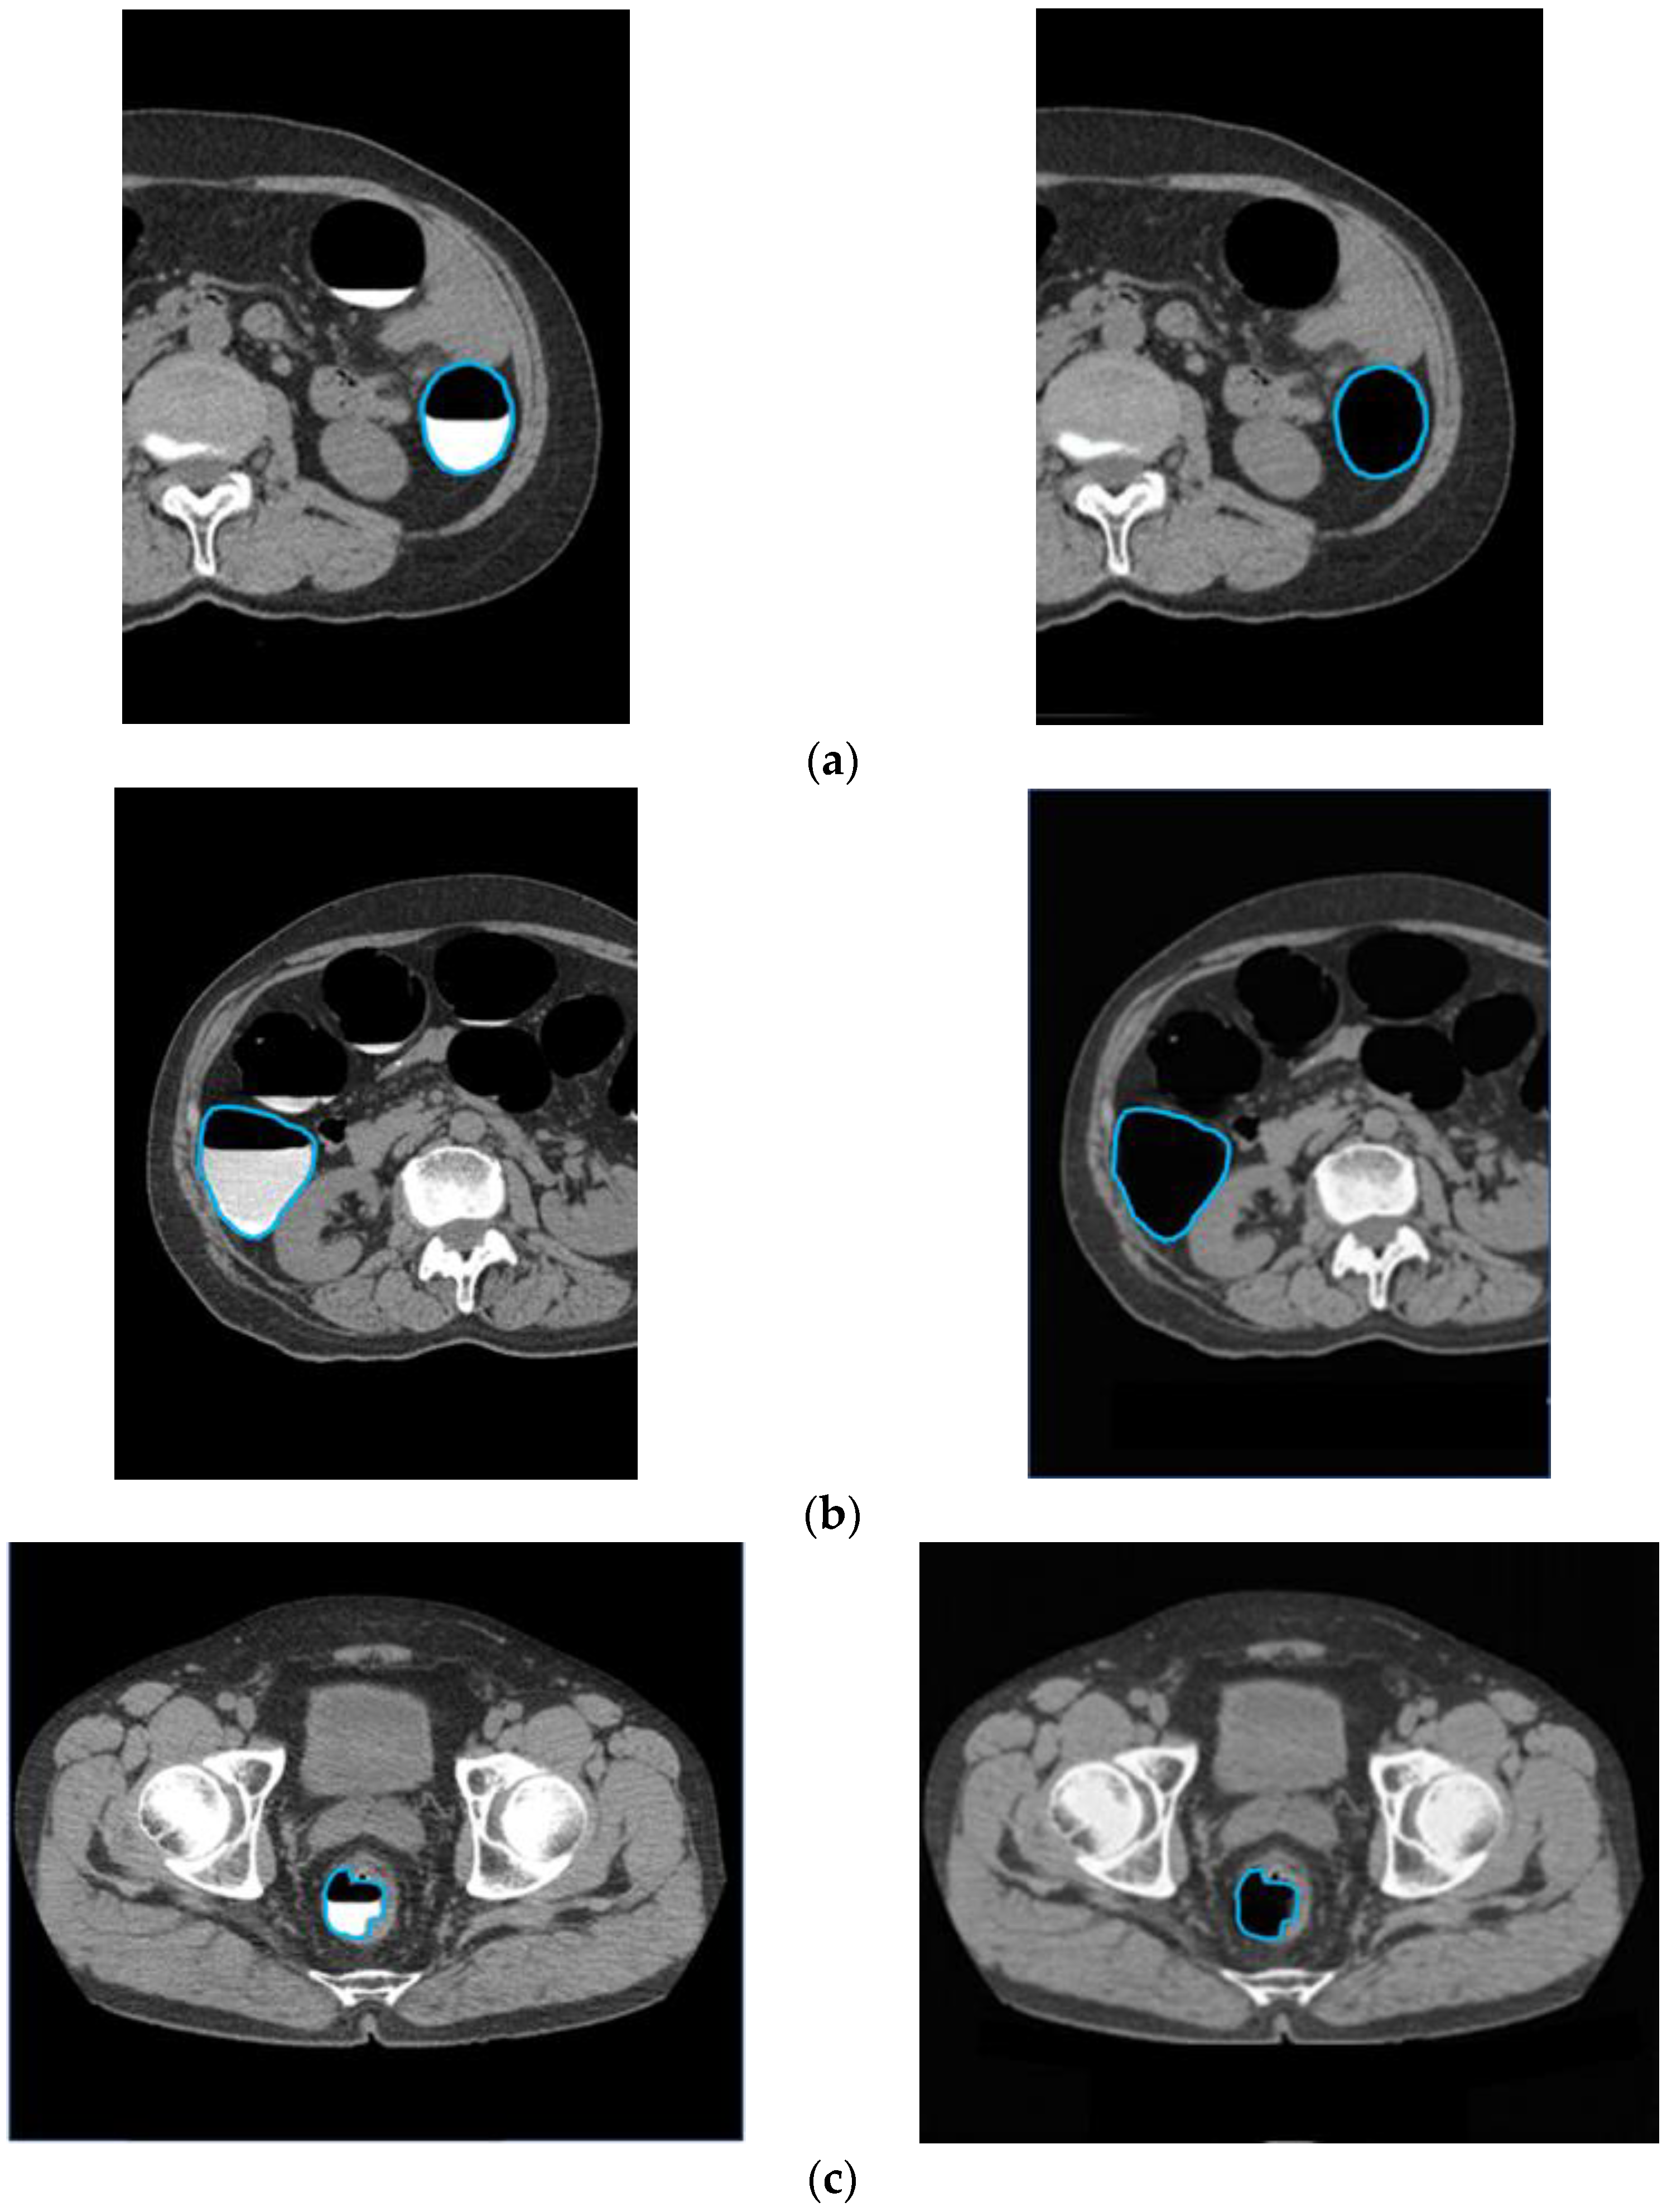

To confirm that an excess area was not removed when the barium was removed, an outline of the intestinal tract wall surface was drawn and overlapped with the original CTC image and the CycleGAN-generated image, as shown in Figure 12. In cases with good barium pretreatment (Figure 12a), poor pretreatment (Figure 12b), and lesions (Figure 12c), the intestinal wall, and lesions were not removed, and only barium was selectively removed, indicating that this technique correctly recognized and removed barium.

Figure 12.

Preservation of intestinal information by barium removal (Left: Input image and Right: output image.) (a) Good pretreatment; (b) bad pretreatment; and (c) image with lesion.